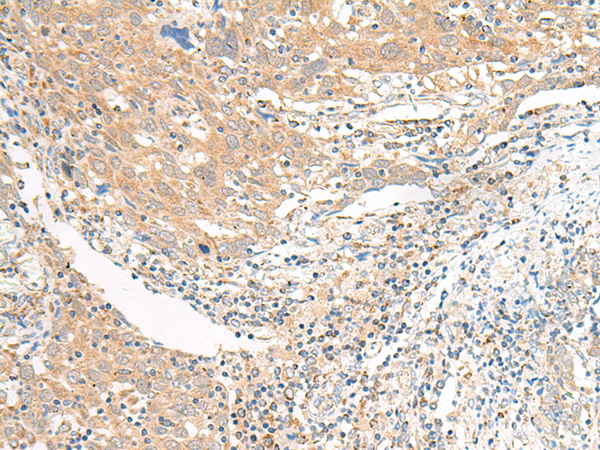

IHC positive control: |

Human colorectal cancer and Human cervical cancer |